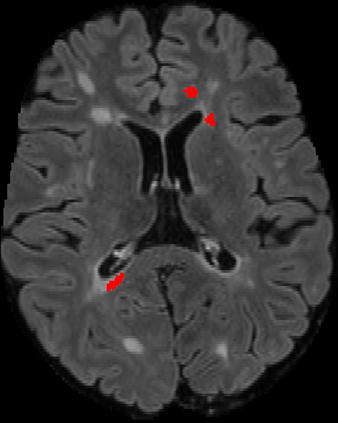

Assessment of lesions and their longitudinal progression from brain magnetic resonance (MR) images plays a crucial role in diagnosing and monitoring multiple sclerosis (MS). Machine learning models have demonstrated a great potential for automated MS lesion segmentation. Training such models typically requires large-scale high-quality datasets that are consistently annotated. However, MS imaging datasets are often small, segregated across multiple sites, with different formats (cross-sectional or longitudinal), and diverse annotation styles. This poses a significant challenge to train a unified MS lesion segmentation model. To tackle this challenge, we present SegHeD, a novel multi-dataset multi-task segmentation model that can incorporate heterogeneous data as input and perform all-lesion, new-lesion, as well as vanishing-lesion segmentation. Furthermore, we account for domain knowledge about MS lesions, incorporating longitudinal, spatial, and volumetric constraints into the segmentation model. SegHeD is assessed on five MS datasets and achieves a high performance in all, new, and vanishing-lesion segmentation, outperforming several state-of-the-art methods in this field.